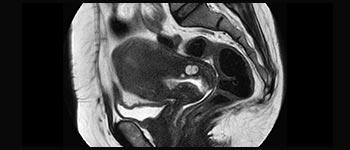

Encuentre la aplicación clínica adecuada a sus necesidades